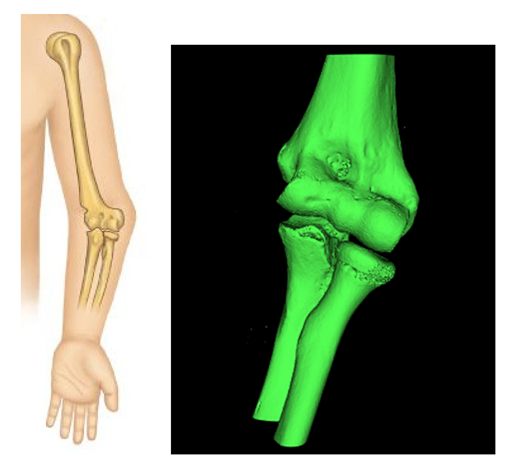

To be able to process the anatomical components on CREO, the import of the STL file from Meshmixer is not enough. This format, in fact, represents an object whose surface has been discretized in triangles and it is not recognized as a real solid used by 3D mechanical modeling programs; CREO is therefore able to open the file but not to process it, if not trivially, providing various views and sections. To make the model a real solid, recognizable by the program, a saving by converting the file into “Shrinkwrap” type is used (Figure 4):

Figure 4.

Save with Shrinkwrap.

As seen below, to define the references (Figure 7, Figure 8, Figure 9, Figure 10 and Figure 11), complex solids must be approximated to simpler geometries; hence, it will be possible to trace the center planes and points of interest as shown in the figure. Creo allows the selection of each mesh vertex; in this way it can characterize the models in a very precise way and highlight relevant anatomical sections, such as epicondyles or diaphysis axes in long bones.

Figure 7.

Starting model for CREO simulation.